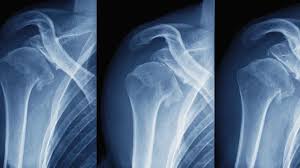

Shoulder dislocation occurs when the upper arm bone pops out of the shoulder socket, often due to trauma or overextension. Dr. Akhila Sunder offers expert evaluation and treatment for both first-time and recurrent dislocations to restore joint stability and prevent further damage.

Depending on the severity and frequency of dislocation, treatment may involve manual repositioning, minimally invasive stabilization techniques, or arthroscopic surgery to repair torn ligaments and reinforce the joint capsule.

Our approach begins with advanced imaging to assess the extent of the injury and tailor the most effective treatment plan—ensuring lasting joint alignment and reduced risk of recurrence.